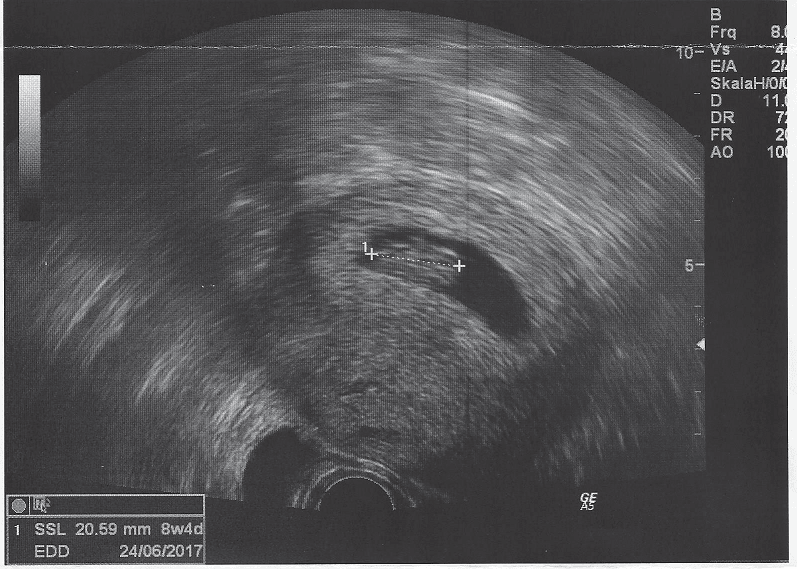

Wszystko jest w najlepszym porządku, Mrówka ma już 20 mm i lekarka jest bardzo zadowolona, dzidzia odpowiada wiekiem dokładnie 8+4. Powiedziała, że ryzyko poronienia wynosi teraz poniżej 5% i wreszcie, wreszcie!, "pozwoliła" nam się cieszyć :)

Zobacz załącznik 783275